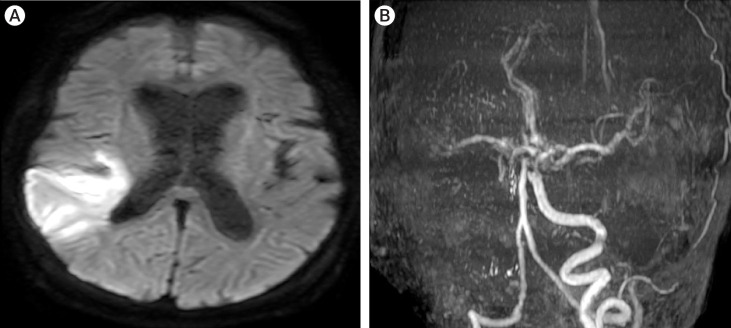

机械血栓切除术导致的远端栓塞是一种常见的并发症,直接导致预后不良。因此,在机械血栓切除术中尽可能减少远端栓塞非常重要。EmboTrap III 可作为一种过滤器,防止血栓体积较大的患者出现远端栓塞。在此,我们报告了一个提示性病例的结果,并提供了一个血管模型的实验数据。患者是一名 78 岁的女性,因主诉构音障碍和左侧偏瘫(包括面瘫)而急诊入院。经检查,她被诊断为右侧串联病变的大血管闭塞性急性缺血性脑卒中,并接受了机械性血栓切除术。根据闭塞部位周围的血流淤滞情况,推测可能存在大量继发性血栓,而且由于颈内动脉再通造成远端栓子,神经症状恶化也是一个令人担忧的问题。SEIMLESS 技术是在使用 EmboTrap III 的远端保护下进行的。没有出现远端栓塞或神经症状恶化,预后良好。这一结果表明,使用 EmboTrap III 在远端保护下进行 PTA 可能有助于预防远端栓塞。

Distal embolus due to mechanical thrombectomy is a frequent complication and directly results in a poor prognosis. Therefore, it is important to decrease distal embolus as much as possible in mechanical thrombectomy. EmboTrap III may be useful as a filter to prevent distal embolus in patients with a large volume of thrombus. Here, we report the results of one suggestive case and we also provide experimental data from a vessel model. The patient was a 78-year-old female who was admitted to hospital as an emergency case with chief complaints including dysarthria and left hemiplegia, including facial paralysis. She was diagnosed as large vessel occlusion-acute ischemic stroke with right tandem lesions by workup and underwent mechanical thrombectomy. A large volume of secondary thrombus due to flow stasis was assumed based around the occlusion site, and worsening of neurological symptoms was a concern due to distal embolus caused by recanalization of the cervical internal carotid artery. The SEIMLESS technique was performed under distal protection using EmboTrap III. There was no distal embolus or deterioration of neurological symptoms, and a good prognosis was achieved. This outcome suggests that PTA under distal protection using EmboTrap III may be useful for prevention of distal embolus.